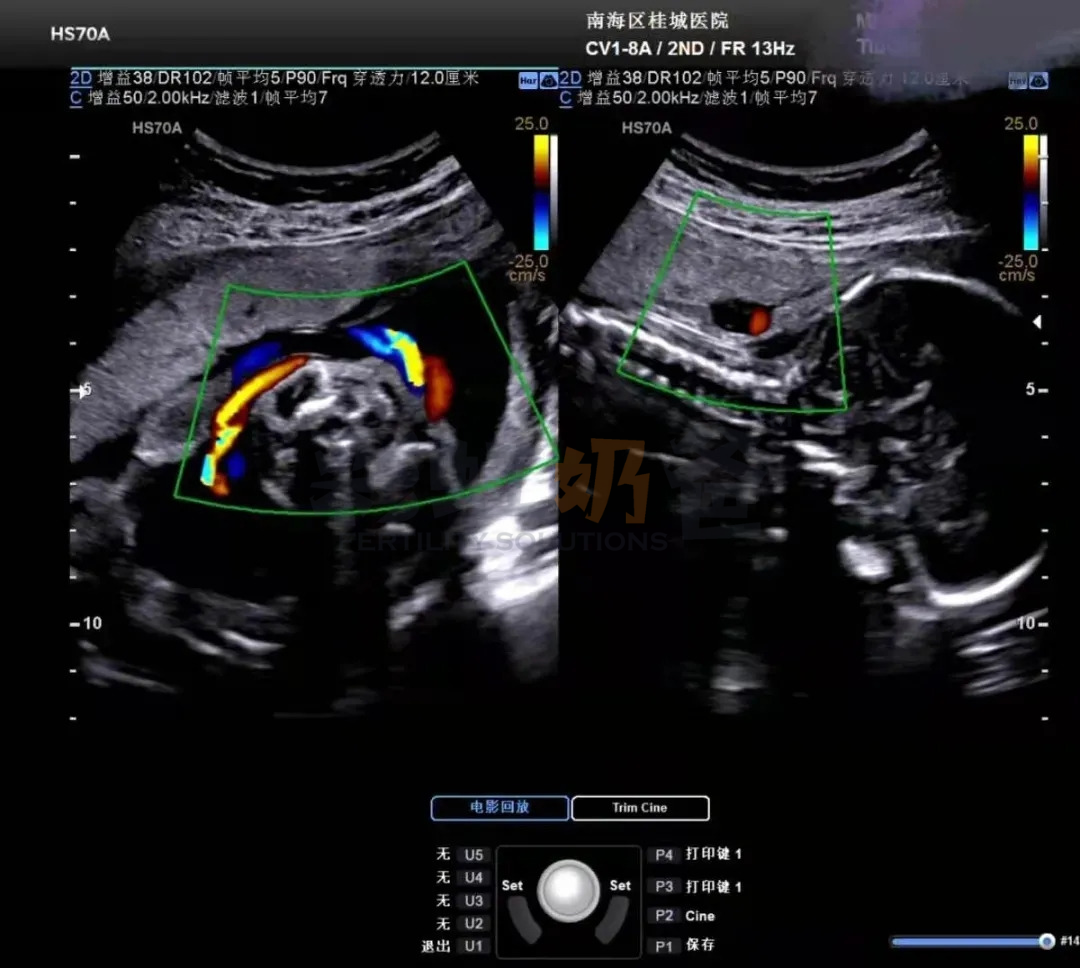

彩超也是一种二维超声B超,但是需要知道的是,它并不是彩色的,依旧是黑白,之所以叫彩超是因为会用彩色标注心脏、血流等指标,可以方便医生的检查,更好的观察胎儿是否异常。在清晰度这一块儿,彩超的分辨会比B超略高一些。